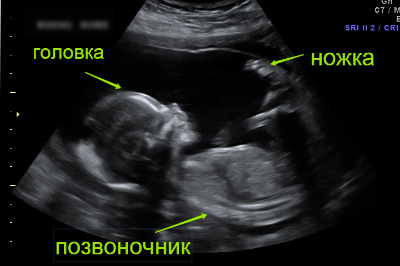

- Фото УЗИ плода

На этом сроке, как правило, происходит одно из наиболее волнительных событий за всю беременность – будущие родители получают возможность узнать пол своего малыша, послушать, как бьется его сердечко.

Кроме этого, на УЗИ уже можно увидеть возможные пороки и отклонения в развитии и предупредить их, поэтому беременным женщинам настоятельно рекомендуется пройти это обследование. Подробнее о скрининге второго триместра читайте здесь.

Фото УЗИ плода

измерить параметры плода;

-

узнать размеры частей тела будущего ребенка;

-

оценить функционирование его органов;

-

оценить состояние плаценты;

-

узнать пол малыша;

-

выявить возможные внутриутробные инфекции и пороки развития.

Очень важно оценить количество и качество околоплодной жидкости, маточный тонус, сердечный ритм плода и т .д. Все эти показатели позволят сделать вывод о состоянии здоровья малыша.

Очень важно оценить количество и качество околоплодной жидкости, маточный тонус, сердечный ритм плода и т .д. Все эти показатели позволят сделать вывод о состоянии здоровья малыша.

К этому времени уже готовы результаты скрининга, но адекватно оценить их можно только при помощи специализированных программ, которые соединяют воедино все показатели.

Подробнее о скрининге второго триместра читайте здесь.